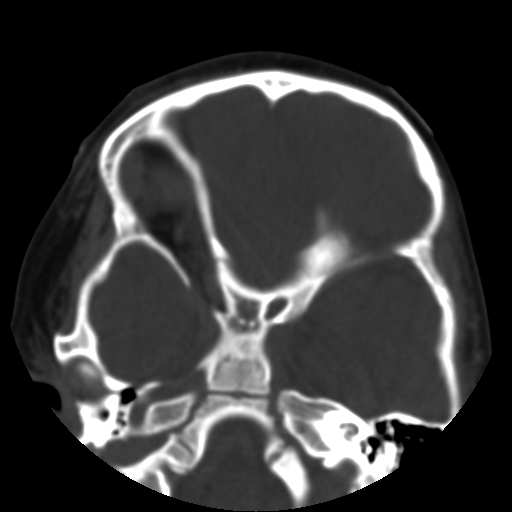

以下是引用深泽交通医院在2009-10-16 8:25:00的发言:[br]右眼环出血伴异物

以下是引用卜一在2009-10-16 15:01:00的发言:[br]右眼球挫裂伤伴异物!

以下是引用拾荒者在2009-10-17 18:38:00的发言:[br]鼻面部皮下积气,右侧睑缘及眼球壁高密度异物影,左侧眼球壁晶状体内侧缘处是圆形低密度影。低密度异物?应提请眼科医生注意。